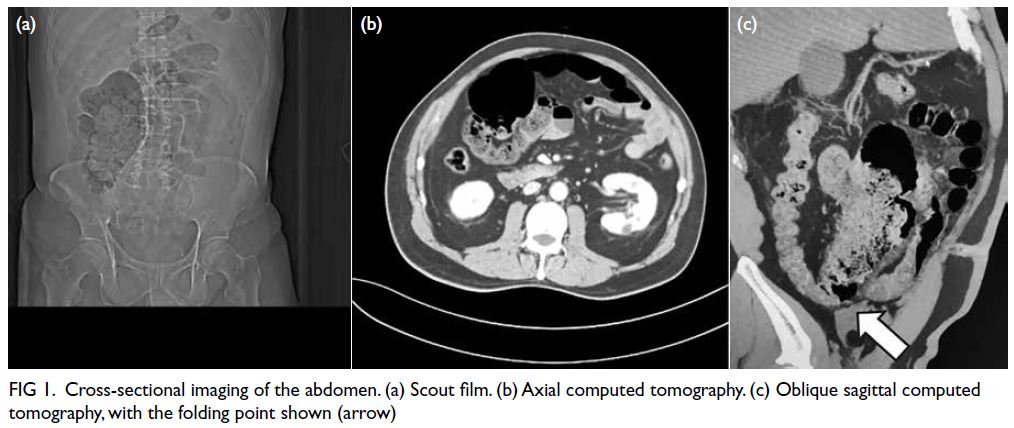

Computed tomography revealed a distended

gallbladder, oedematous gallbladder wall thickening

and pericholecystic inflammatory fat stranding

without gallstones; the caecum and a segment of

terminal ileum were prominently dilated, measuring

up to 8.4 cm and 2.8 cm, respectively, with a gradual

transition zone identified between the caecum and ascending colon (Fig 1). Initial radiology suggested

acute cholecystitis and faecal impaction. However,

after further clarification and in the absence of any

mesenteric rotation or twisting, a diagnosis of caecal

volvulus (bascule type) could not be made.

Figure 1. Cross-sectional imaging of the abdomen. (a) Scout film. (b) Axial computed tomography. (c) Oblique sagittal computed tomography, with the folding point shown (arrow)